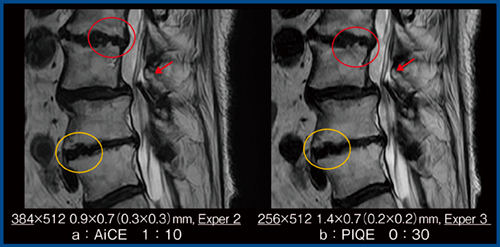

図6は,撮像時間1分10秒の従来画像(AiCE適用:a)と,30秒のPIQE画像(b)の比較である。描出能はほぼ同等であるが,PIQEの方が馬尾(図6←)が鮮明に描出され,椎間板のコントラストが明瞭なため,当院ではPIQEの画像を使用している。なお,微小な椎体終板下骨の突起(図6○)は,PIQEでは明瞭であるが,AiCEでは鈍化しているように見える。一方,AiCEで描出できている2つの突起が,PIQEでは1つに見える(図6○)。PIQEにおいて,従来描出されていた画像情報の一部が強調あるいは見えづらくなっているのは,フェーズエンコード方向のマトリックスの違いやパラレルイメージング法である「Expanded SPEEDER(Exsper)」の影響が考えられる。そのため,シーケンスの設定に当たっては,PIQEに適した設定が必要であると考える。

図6 従来画像(AiCE適用)と撮像時間を短縮したPIQE画像の比較